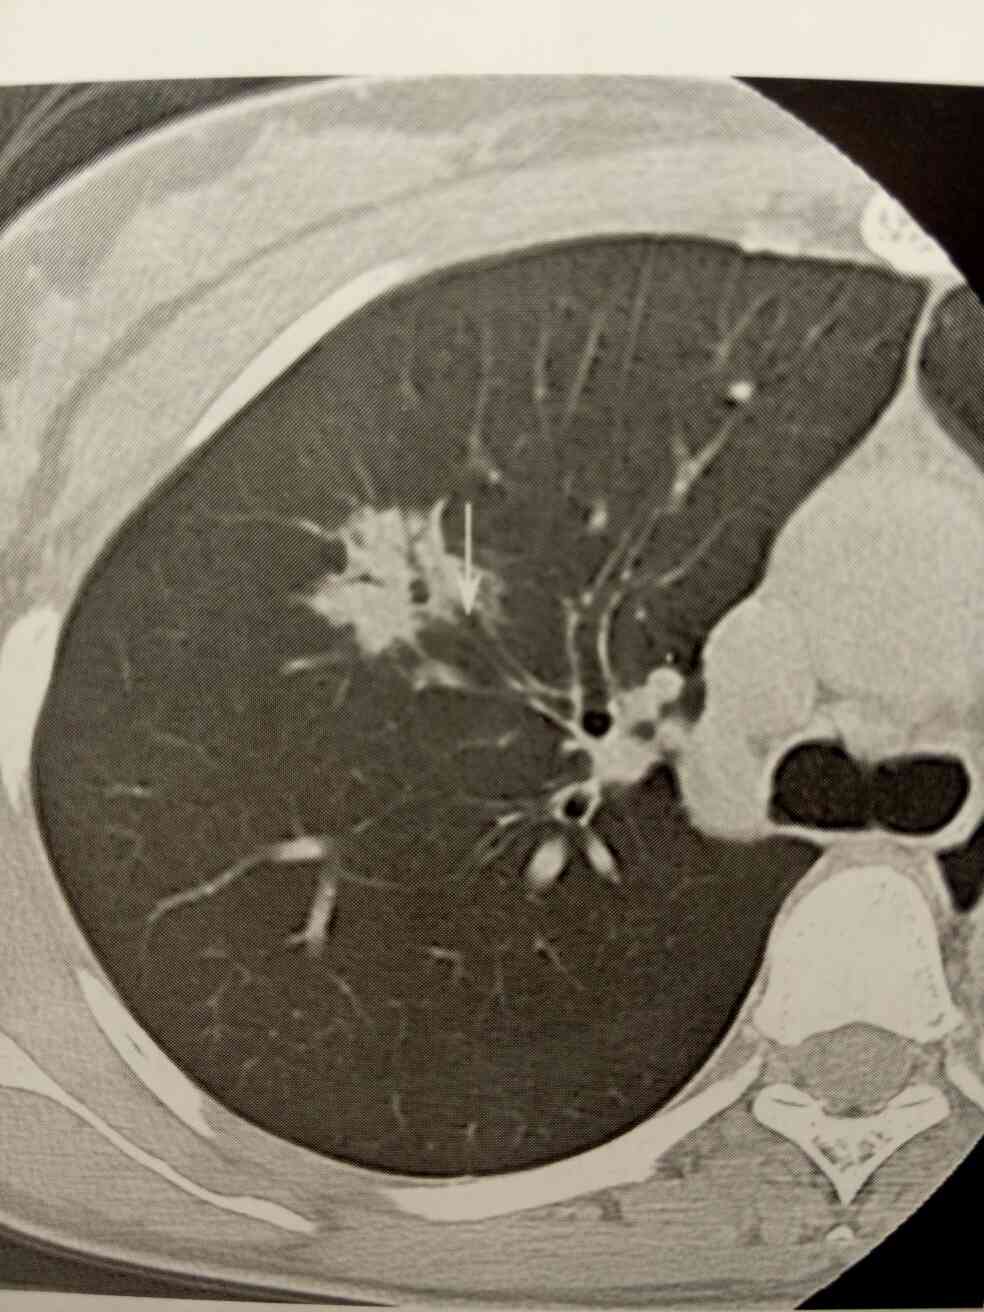

女,64岁,09年因咳嗽CT发现两肺结节,当时考虑转移瘤,但患者无肿瘤病史,拒绝进一步检查。于3个月、半年、二年复查,无明显变化。今天再次复查,如下图,无明显变化。

肺癌支气管中断。右肺上叶肺癌可见细支气管在进去结节前中断,箭头所指。